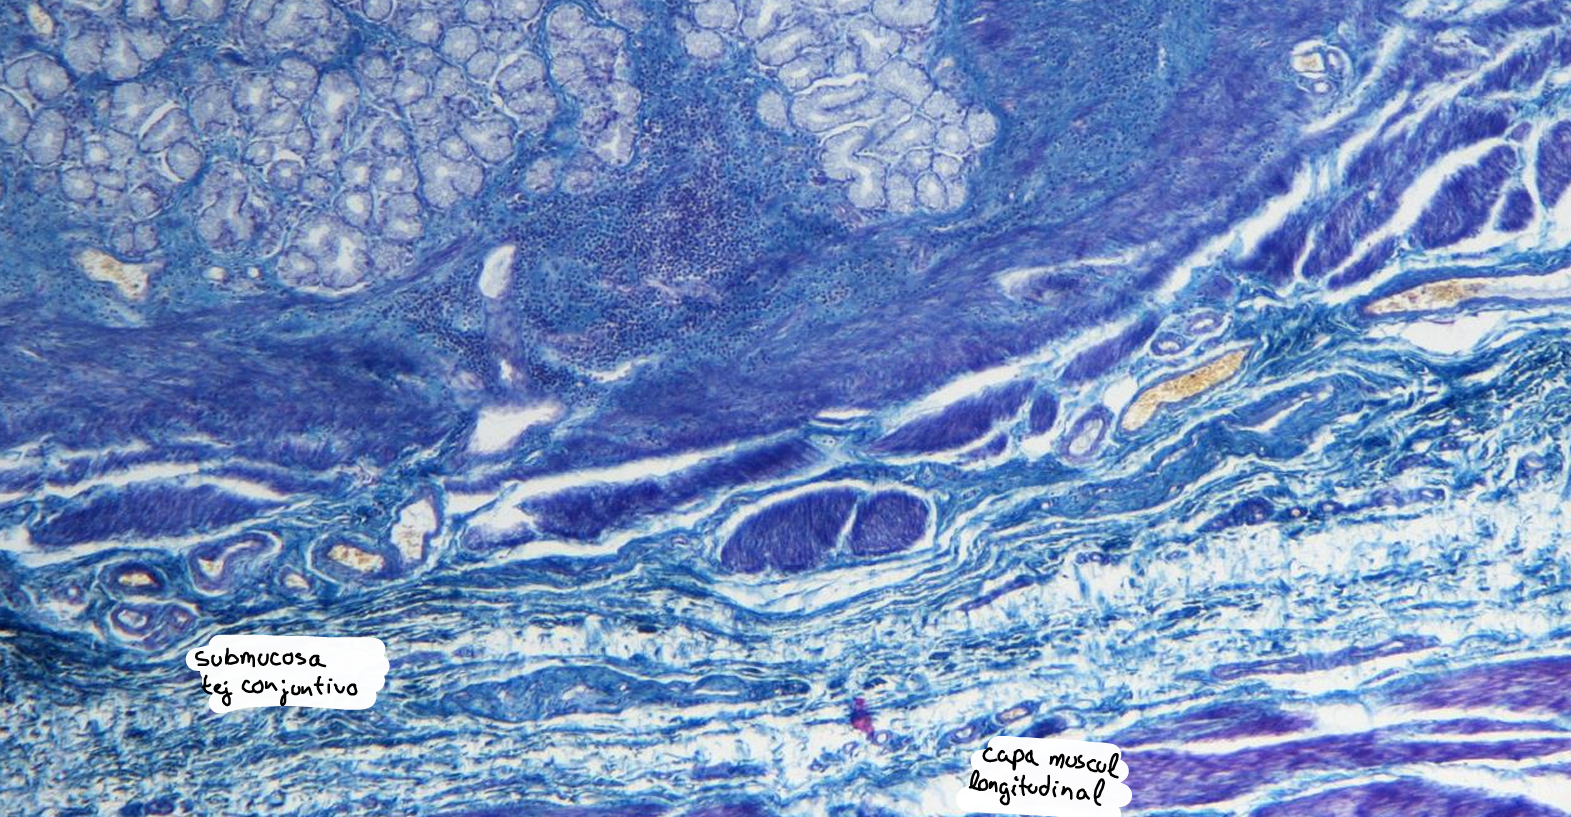

intestino grueso es la parte final del sistema digestivo, encargada de absorber agua y electrolitos, además de formar y eliminar las heces.

intestino grueso

colon